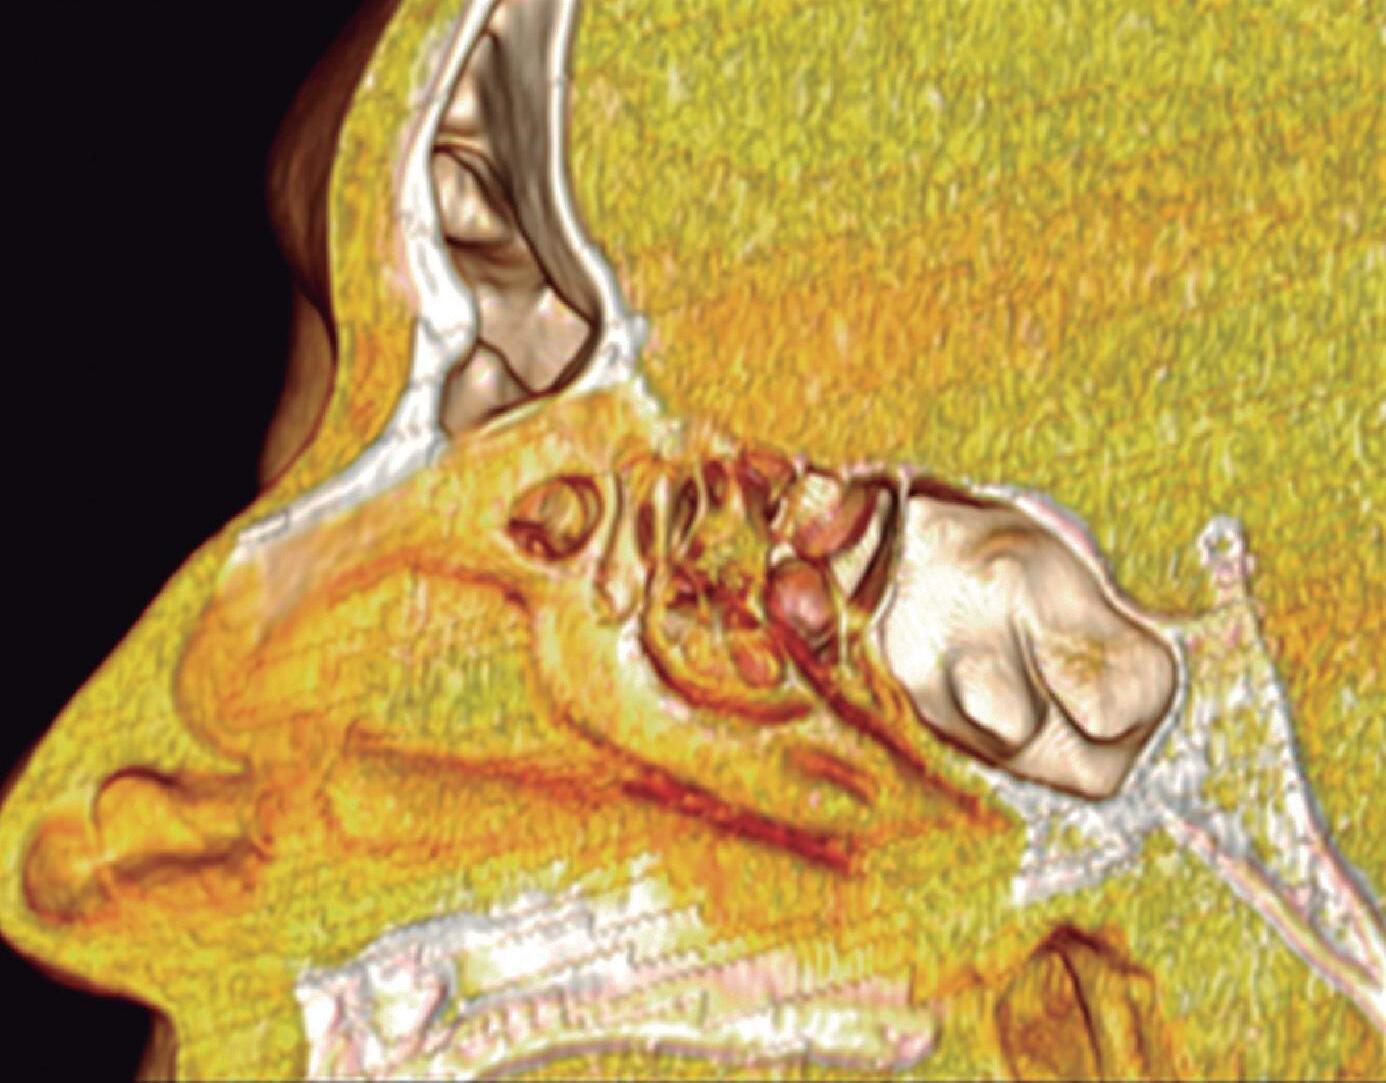

1-4. TC e reconstrução 3D com destaque para estrutura etmoidal (em vermelho), funcionando como câmaras de baixa pressão para drenagem do seio maxilar.

1-7. TC com reconstrução 3D mostrando em vermelho apenas o seio etmoidal e não o osso etmoidal, e sua relação com a fossa nasal, o seio maxilar, órbita e fossa anterior.